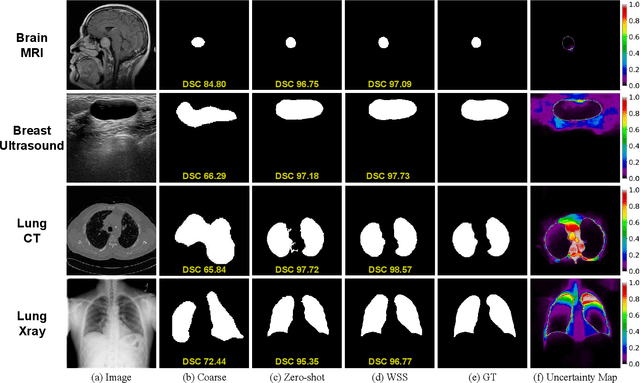

Abstract:Segmentation of anatomical structures and pathological regions in medical images is essential for modern clinical diagnosis, disease research, and treatment planning. While significant advancements have been made in deep learning-based segmentation techniques, many of these methods still suffer from limitations in data efficiency, generalizability, and interactivity. As a result, developing precise segmentation methods that require fewer labeled datasets remains a critical challenge in medical image analysis. Recently, the introduction of foundation models like CLIP and Segment-Anything-Model (SAM), with robust cross-domain representations, has paved the way for interactive and universal image segmentation. However, further exploration of these models for data-efficient segmentation in medical imaging is still needed and highly relevant. In this paper, we introduce MedCLIP-SAMv2, a novel framework that integrates the CLIP and SAM models to perform segmentation on clinical scans using text prompts, in both zero-shot and weakly supervised settings. Our approach includes fine-tuning the BiomedCLIP model with a new Decoupled Hard Negative Noise Contrastive Estimation (DHN-NCE) loss, and leveraging the Multi-modal Information Bottleneck (M2IB) to create visual prompts for generating segmentation masks from SAM in the zero-shot setting. We also investigate using zero-shot segmentation labels within a weakly supervised paradigm to enhance segmentation quality further. Extensive testing across four diverse segmentation tasks and medical imaging modalities (breast tumor ultrasound, brain tumor MRI, lung X-ray, and lung CT) demonstrates the high accuracy of our proposed framework. Our code is available at https://github.com/HealthX-Lab/MedCLIP-SAMv2.

Abstract:Medical image segmentation of anatomical structures and pathology is crucial in modern clinical diagnosis, disease study, and treatment planning. To date, great progress has been made in deep learning-based segmentation techniques, but most methods still lack data efficiency, generalizability, and interactability. Consequently, the development of new, precise segmentation methods that demand fewer labeled datasets is of utmost importance in medical image analysis. Recently, the emergence of foundation models, such as CLIP and Segment-Anything-Model (SAM), with comprehensive cross-domain representation opened the door for interactive and universal image segmentation. However, exploration of these models for data-efficient medical image segmentation is still limited, but is highly necessary. In this paper, we propose a novel framework, called MedCLIP-SAM that combines CLIP and SAM models to generate segmentation of clinical scans using text prompts in both zero-shot and weakly supervised settings. To achieve this, we employed a new Decoupled Hard Negative Noise Contrastive Estimation (DHN-NCE) loss to fine-tune the BiomedCLIP model and the recent gScoreCAM to generate prompts to obtain segmentation masks from SAM in a zero-shot setting. Additionally, we explored the use of zero-shot segmentation labels in a weakly supervised paradigm to improve the segmentation quality further. By extensively testing three diverse segmentation tasks and medical image modalities (breast tumor ultrasound, brain tumor MRI, and lung X-ray), our proposed framework has demonstrated excellent accuracy.